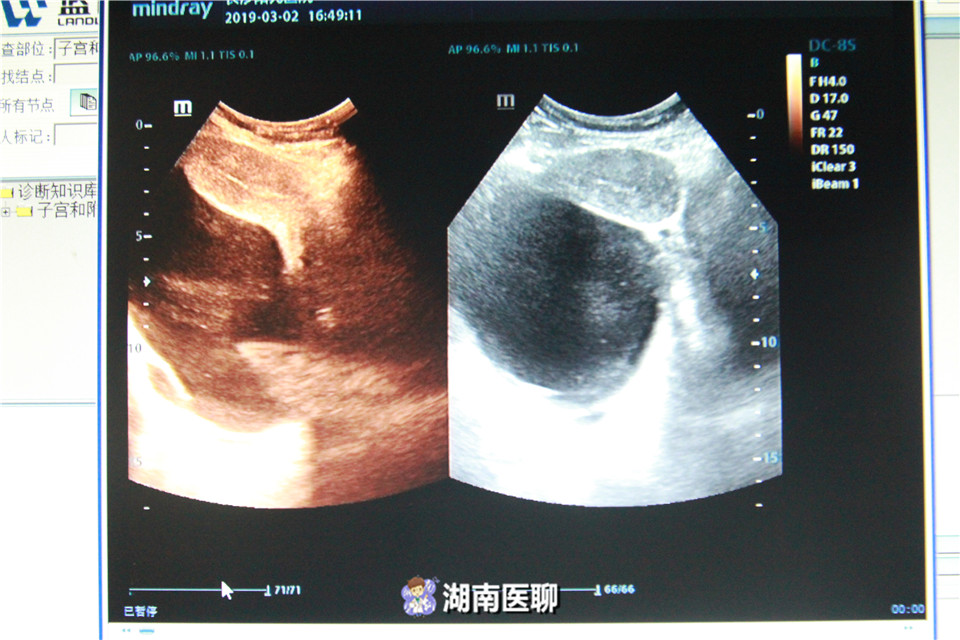

B超探查以及输卵管造影检查发现,刘女士右侧输卵管和卵巢系膜周边竟然有一个18厘米大的囊性包块,如足球般大小。

通过最终病理化验,这个巨大的囊性包块确诊为卵巢浆液性囊腺瘤,是卵巢肿瘤的一种。